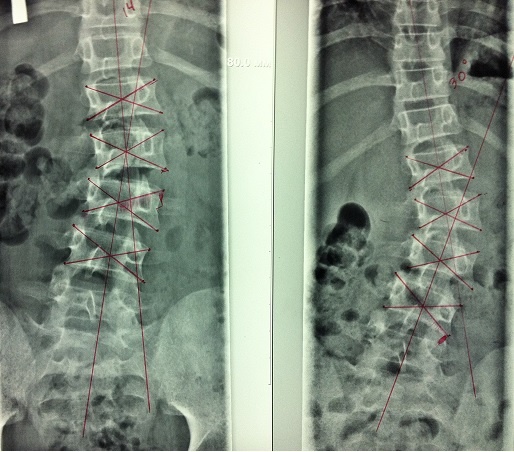

Определение стабильности сколиоза:

1. Сколиоз фиксированный (стабильный) - угол сколиоза в положении пациента лежа и стоя не изменяется

2. Сколиоз нефиксированный (нестабильный) – угол сколиоза в положении пациента лежа, т.е. при разгрузке позвоночника уменьшается

Рентгенограмма позвоночника прямая проекция лежа и стоя. Нефиксированный сколиоз.